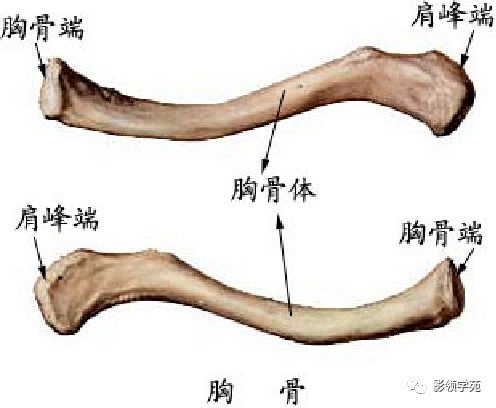

骨骼系统

骨骼系统